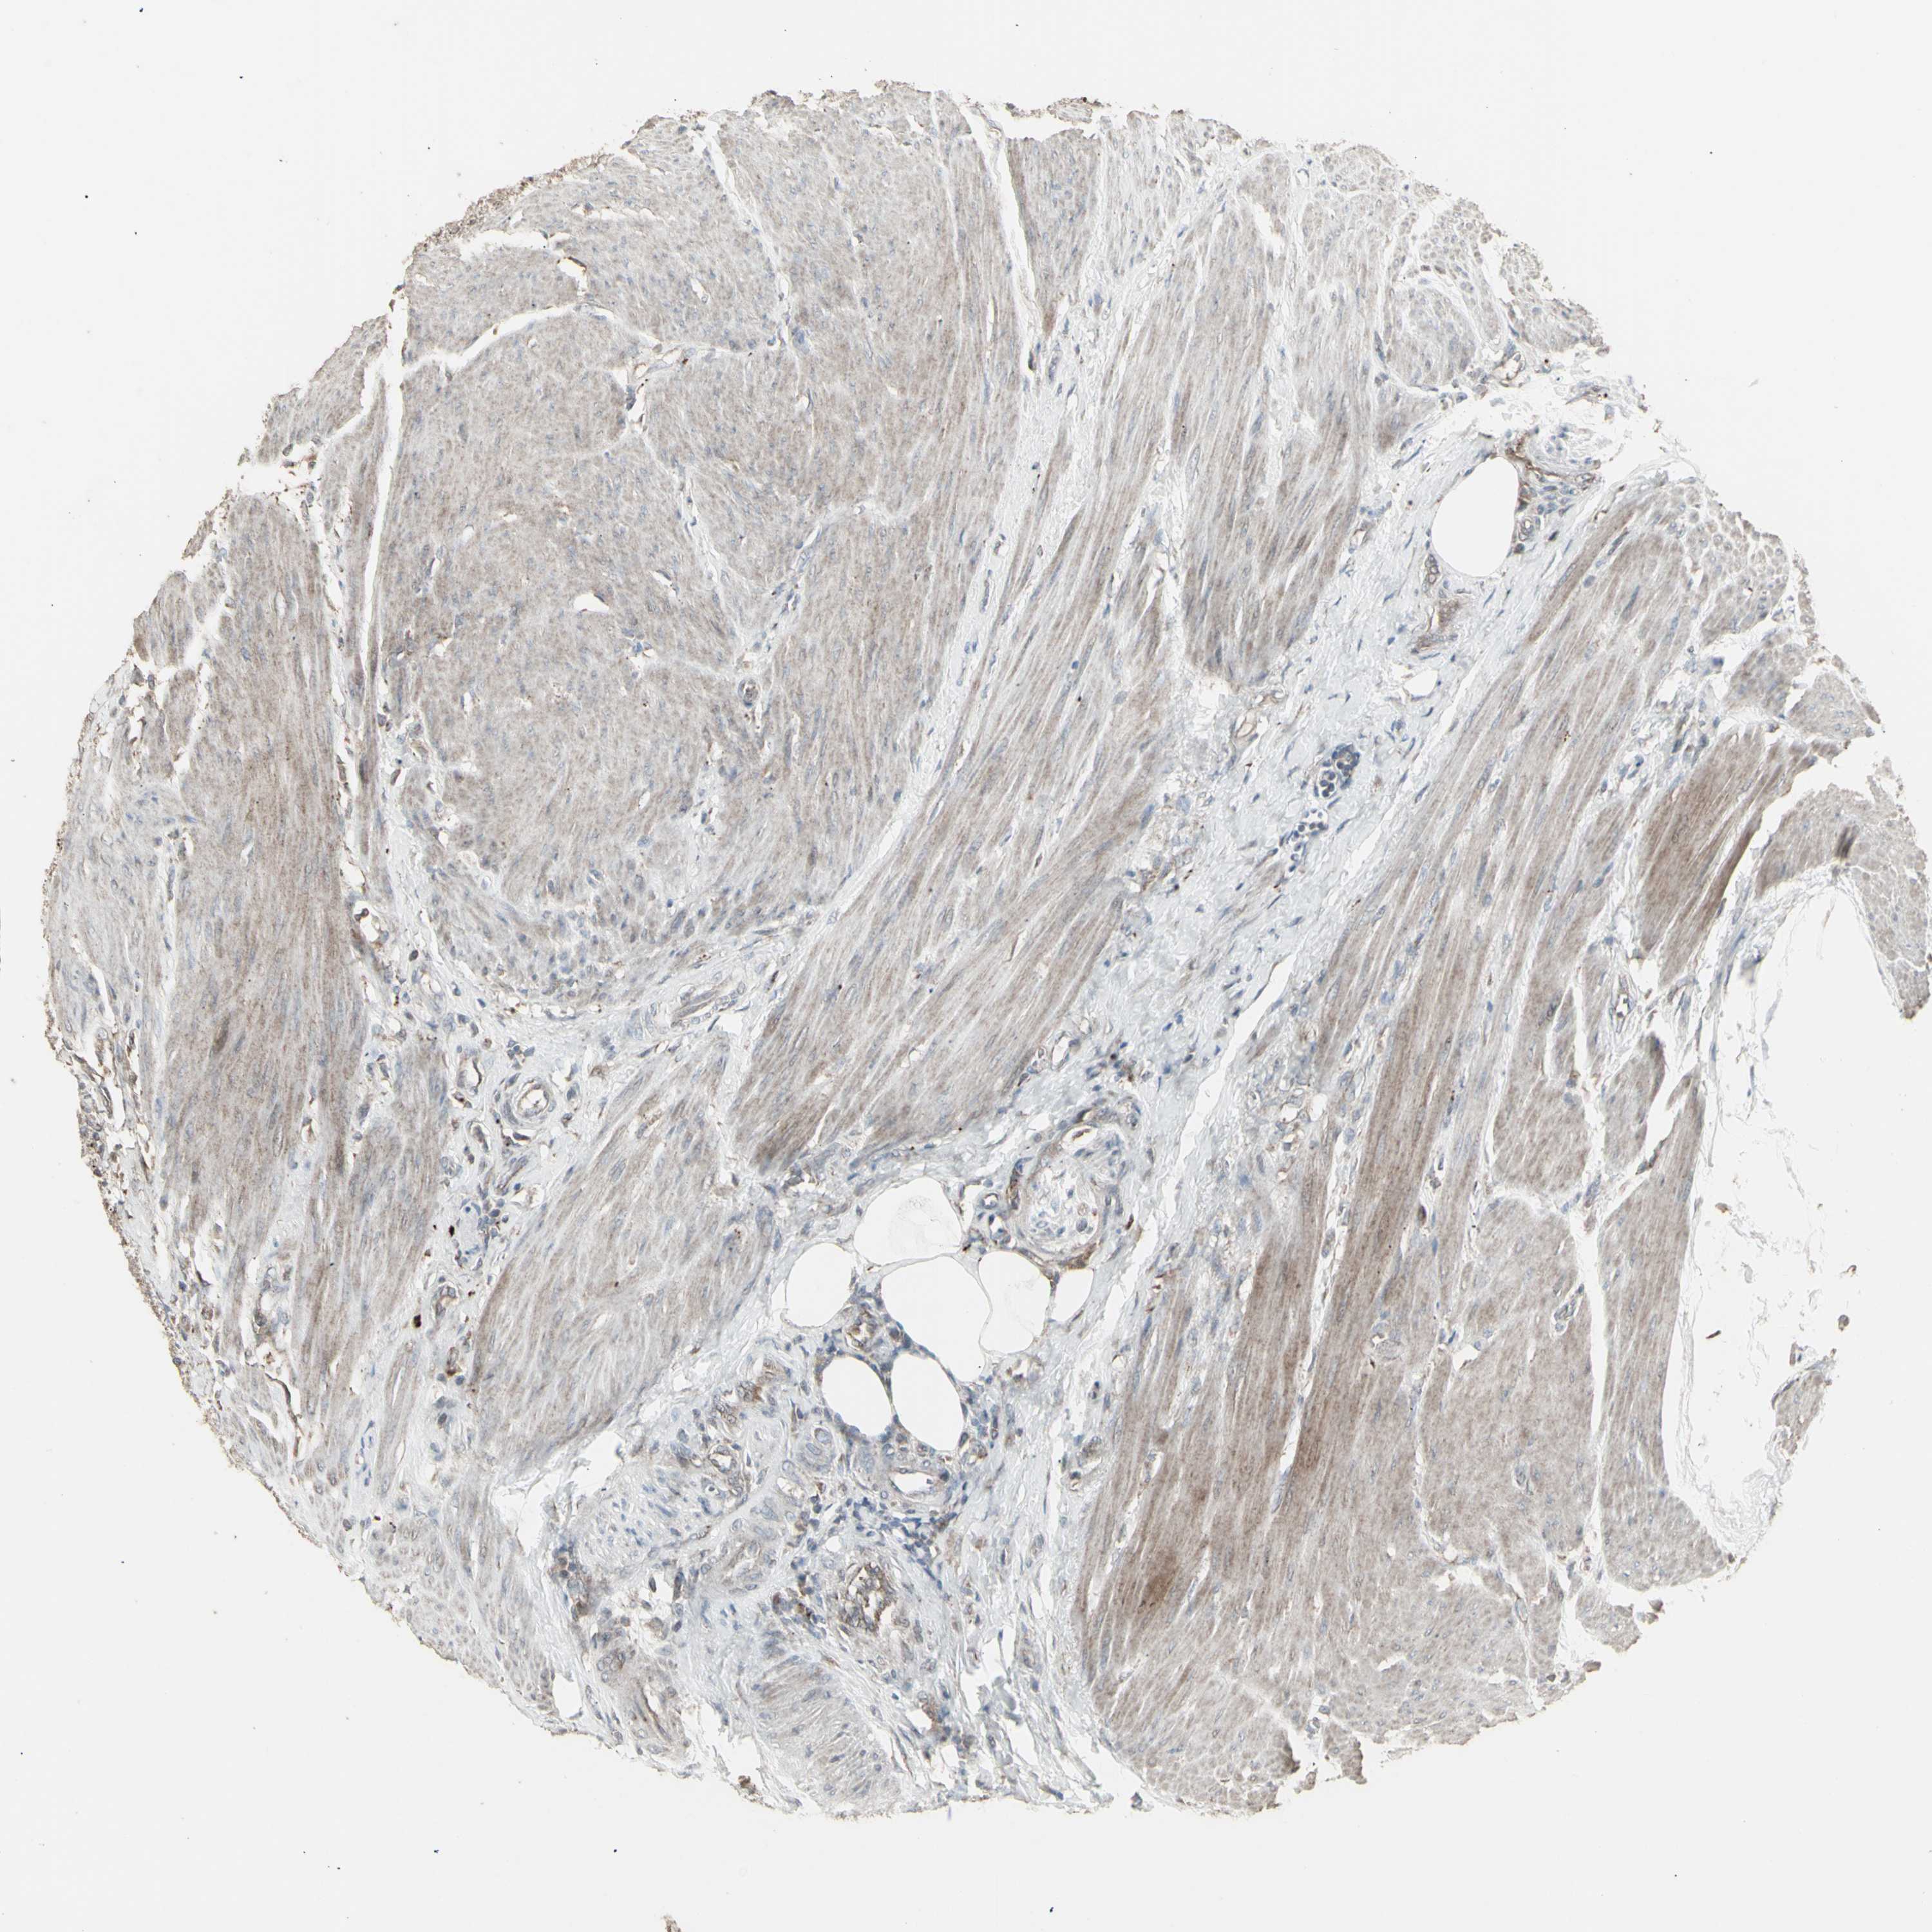

UROTHELIAL CANCER - Protein expressioni

A mouse-over function shows sample information and annotation data. Click on an image to view it in a full screen mode. Samples can be filtered based on level of antibody staining by selecting one or several of the following categories: high, medium, low and not detected. The assay and annotation is described here.

Antibody stainingi

Antibody staining in the annotated cell types in the current human tissue is reported as not detected, low, medium, or high, based on conventional immunohistochemistry profiling in selected tissues. This score is based on the combination of the staining intensity and fraction of stained cells.

Each image is clickable and will lead to virtual microscopy that enables deeper exploration of all samples and also displays staining intensity scores, fraction scores and subcellular localization as well as patient and tissue information for each sample.

Antibody HPA002633

Antibody HPA046758

Antibody CAB010906

Urothelial carcinoma, High grade

Urothelial carcinoma, Low grade